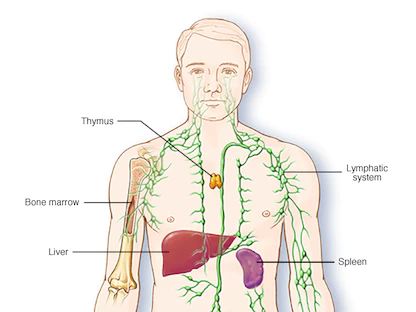

كما اكتشف الباحثون وجود نوع خاص من الخلايا المناعية المرتبطة بالدهون بكثافة داخل الورم، وهو ما قد يلعب دوراً مهماً في تنظيم إنتاج الهرمونات ونمو الورم.